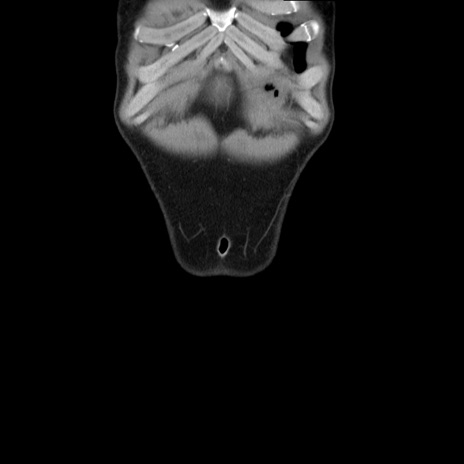

症例36(冠状断像)

【症例】20歳代 男性

【主訴】心窩部痛

【現病歴】今朝より上腹部痛あり。一旦軽快していたが再度出現したため救急要請。昨日夕に白身の魚を含む刺身を食べた。

【身体所見】BP 136/89mmHg、HR 74/min、BT 37.0℃、腹部:膨満、軟、心窩部に圧痛あり。反跳痛なし、筋性防御なし、腸雑音やや亢進あり。

【データ】WBC 17700、CRP 0.48